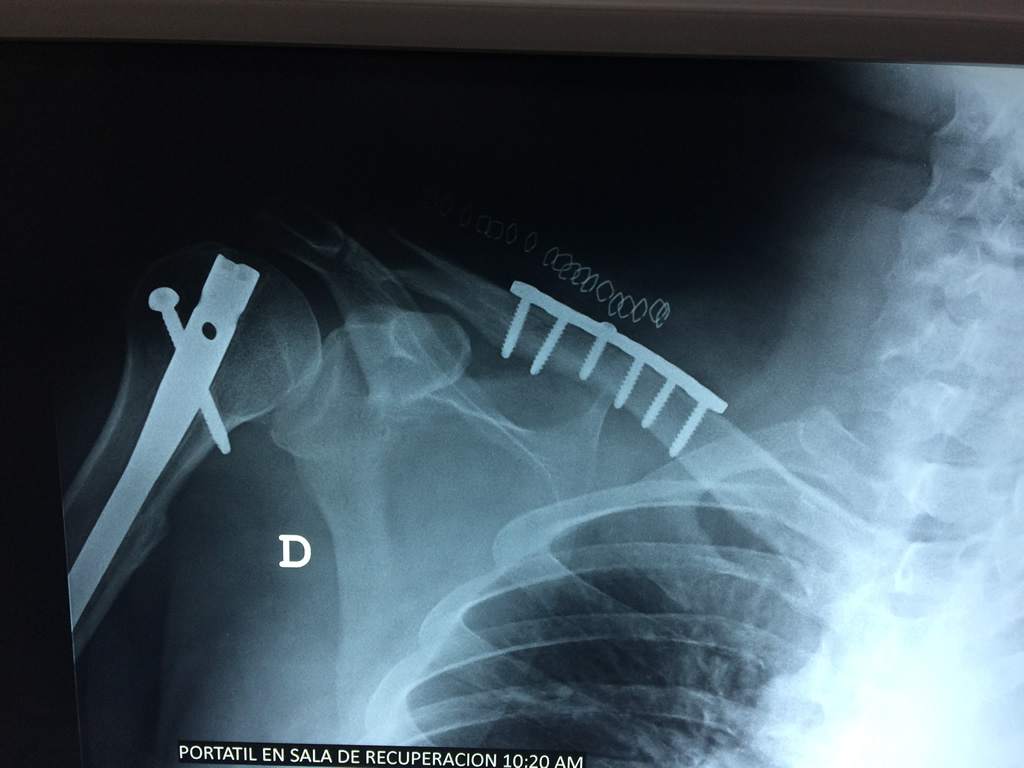

Calcaneo - Clavícula

La clavícula es un hueso largo, con forma de "S" itálica, situado en la parte anterosuperior del tórax. Junto con la escápula forman la cintura escapular. Se puede palpar por toda su longitud y se extiende del esternón al acromion de la escápula, siguiendo una dirección oblicua lateral y posterior.